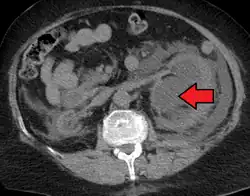

Hydronephrosis due to a kidney stone at the ureteral vesicular junction seen on CT scan